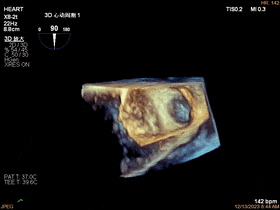

2、人工瓣膜功能的评价:更直观显示人工瓣瓣叶结构(人工瓣有无血栓、血管翳、卡瓣等),人工瓣与周围结构组织关系(有无瓣周漏等)。

人工二尖瓣机械瓣三维图